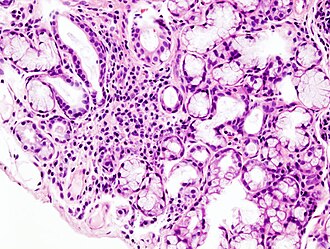

Sjögrenov sindrom je autoimuna bolest koja zahvaća žlijezde i unutarnje organe. Najčešće su zahvaćene žlijezde sa vanjskim izlučivanjem (egzokrine žlijezde) koje proizvode slinu (žlijezde slinovnice) i suze (suzna žlijezda). Uzok nastanka poremećaja u imunološkom sustavu je nepoznat. Bolest se najčešće javlja nakon 40. godine života i češće zahvaća žene. Bolest je dobila naziv po švedskom oftalmologu Henriku Sjögrenu (1899-1986), koji je prvi opisao bolest. Sjögrenov sindrom je često udružen sa drugim reumatskim bolestima ili autoimunim bolestima kao što su reumatski artritis, sustavni eritemski lupus, sustavna skleroza ili Hashimotov tireoiditis. Tada govorimo o sekundarnom Sjögrenovu sindromu.